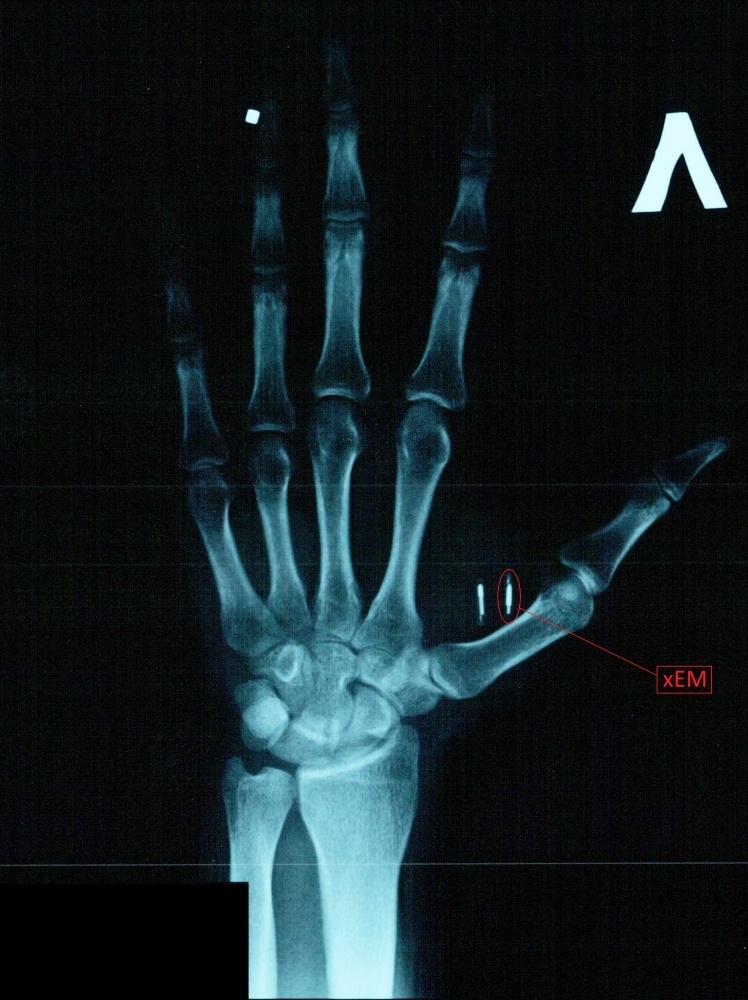

Нет. Рентген в аэропорту не обнаруживает настолько мелкие предметы. Металла в метках ещё меньше, так что металлоискатели их тоже не обнаружат. Противокражные системы не реагируют на все подряд RFID-метки, иначе они срабатывали бы почти на каждого проходящего, ведь какие-либо метки есть при себе почти у всех. Хотя у меня однажды был случай, что противокражная система сработала на пустую перезаписываемую EM-Marine метку. Метки не содержат хоть сколько-то значительного количества ферромагнетиков, так что даже сильнейшие магнитные поля МРТ не нанесут вреда ни импланту, ни его носителю. Что касается КТ/рентгена — как видите, мне удалось успешно сделать рентгеновский снимок руки. Естественно, все импланты по-прежнему работают.

Странным для меня оказалось то, что на рентгене её практически не видно — я ожидал увидеть красивый узор антенны, а оказалось видно только еле заметное круглое уплотнение. Видимо, фольга антенны оказалась слишком тонкой.